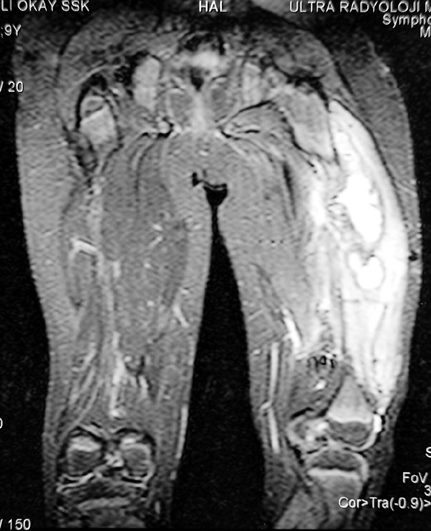

Chronic Osteomyelitis

Musculoskeletal infections are encountered frequently. The treatment of chronic osteomyelitis has changed to a great degree in the last 20 years due to new staging systems, advanced surgical techniques, and supporting treatment methods like hyperbaric oxygen treatment.

Chronic osteomyelitis leads to necrosis of bone and soft tissues. Dead bone is a nidus which hosts pathogenous microorganisms. Defence mechanisms of the host is usually not in optimum condition to deal with microorganisms. Antibiotics can’t reach the infection site because blood flow is disrupted. For these reasons, dead bone has to be completely removed by radical debridement.